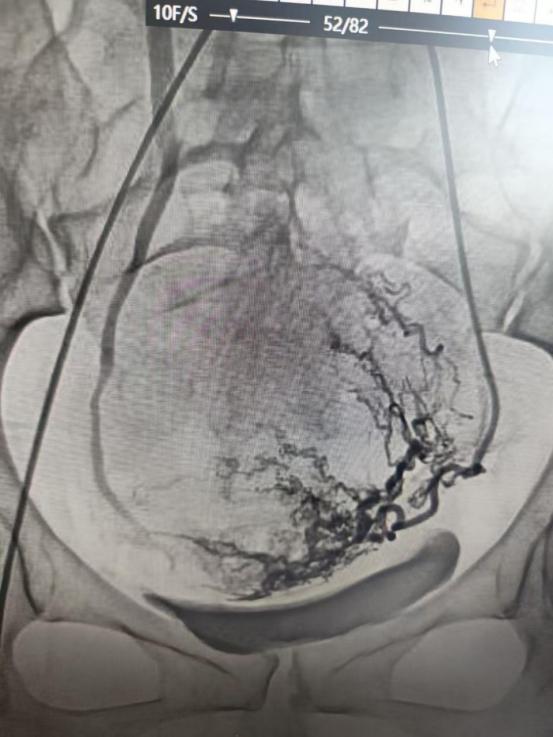

由袁凯主任操作,局部麻醉后经大腿根部针眼大小创口穿刺,将微导管送入子宫动脉,注入可吸收栓塞材料,精准阻断妊娠组织血供,从源头避免大出血,同时保留子宫正常供血,为后续手术保驾护航。